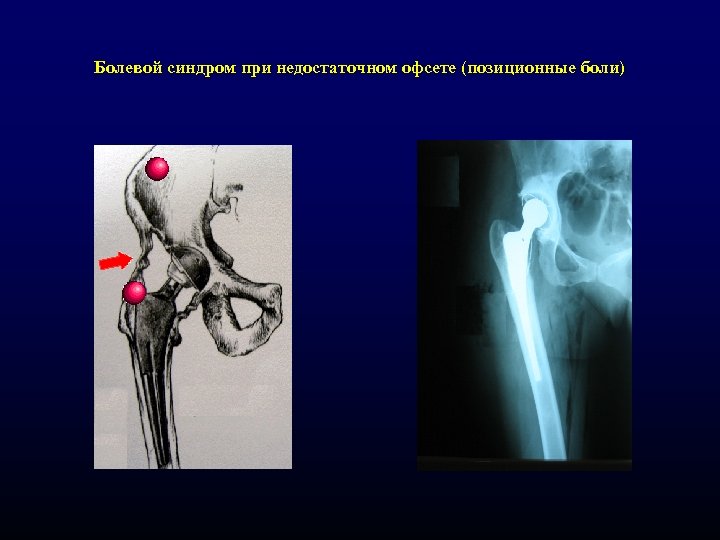

Болевой синдром при недостаточном офсете (позиционные боли) Болевой синдром при недостаточном офсете (позиционные боли)